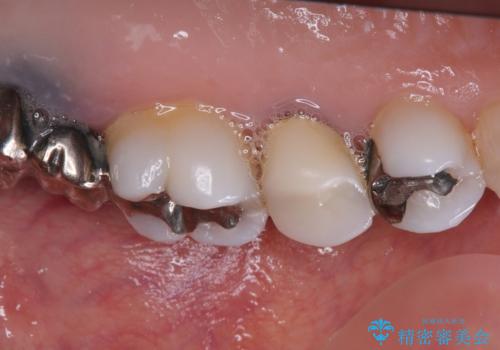

- 奥歯の銀歯とクラウンの縁から見えている歯根を気にして来院された患者様です。

歯根の見えている歯はセラミッククラウンに、詰め物の銀歯が入っている歯はセラミックインレーにて治療を行うこととしました。